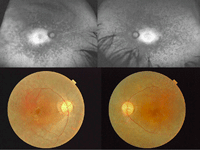

Como ejemplo de cavidades quísticas, en las Figuras 16-21 se muestran dos hermanos varones, de 40 y 45 años de edad, afectos de retinosquisis familiar ligada al X:

-

Varón de 40 años: atrofia central macular bilateral (Figura 16: retinografías, parte superior) y mínima hiperfluorescencia desde tiempos iniciales de la angiografía, que no varía a lo largo del angiograma (Figura 16: angiografía, parte inferior). En la imagen de OCT (Figura 17) se ven grandes cavidades quísticas con pérdida de la arquitectura normal foveal.

Varón de 45 años (Figura 18 y Figura 19): a pesar de tener espacios quísticos maculares escasos en ambos ojos, presentaba una pérdida de la estructura normal de las cuatro bandas en la retina externa, con agudezas visuales de 0,2 en el ojo derecho y 0,1 en el izquierdo.

Figura 16. Retinosquisis familiar ligada al X. Varón de 40 años. Imágenes superiores, retinografías de campo amplio en las que se observa atrofia central macular bilateral. Imágenes inferiores, angiografía fluoresceínica de campo amplio que muestra leve hiperfluorescencia macular desde tiempos iniciales, que no varía a lo largo del angiograma.

Figura 17. Retinosquisis familiar ligada al X. Imagen de OCT del paciente de la Figura 16. La OCT superior corresponde al ojo derecho y la OCT inferior corresponde al ojo izquierdo. En ambos ojos se ven grandes cavidades quísticas que ocupan el espesor completo retiniano, con pérdida de la arquitectura normal foveal.

Figuras 18 y 19. Retinosquisis familiar ligada al X. Ojo derecho (imágenes superiores) y ojo izquierdo (imágenes inferiores) de paciente varón de 45 años de edad, hermano del paciente de las Figuras 16 y 17. En la OCT de ambos ojos se aprecian pequeños espacios quísticos maculares intraretinianos, pero con importante desestructuración de las capas externas de la retina en la zona de la fóvea.

Figura 20.

Figura 21.

Figuras 20 y 21. Retinosquisis familiar ligada al X. Retinografías de campo amplio del ojo derecho (Figura 20) y del ojo izquierdo (Figura 21) del hermano de 45 años de edad. En la retina periférica temporal del ojo derecho (flecha blanca superior), retinosquisis temporal, y tanto en la periferia nasal del ojo derecho como en la temporal de ambos ojos se observan algunos acúmulos de pigmento numular (flechas blancas).

En la retina periférica de ambos pacientes podía apreciarse en la exploración detallada del fondo de ojo una retinosquisis temporal (

Figura 20: retinografía del ojo derecho del hermano mayor) y algunos acúmulos de pigmento numular (

Figura 20 y

Figura 21: retinografía del ojo izquierdo del hermano mayor).